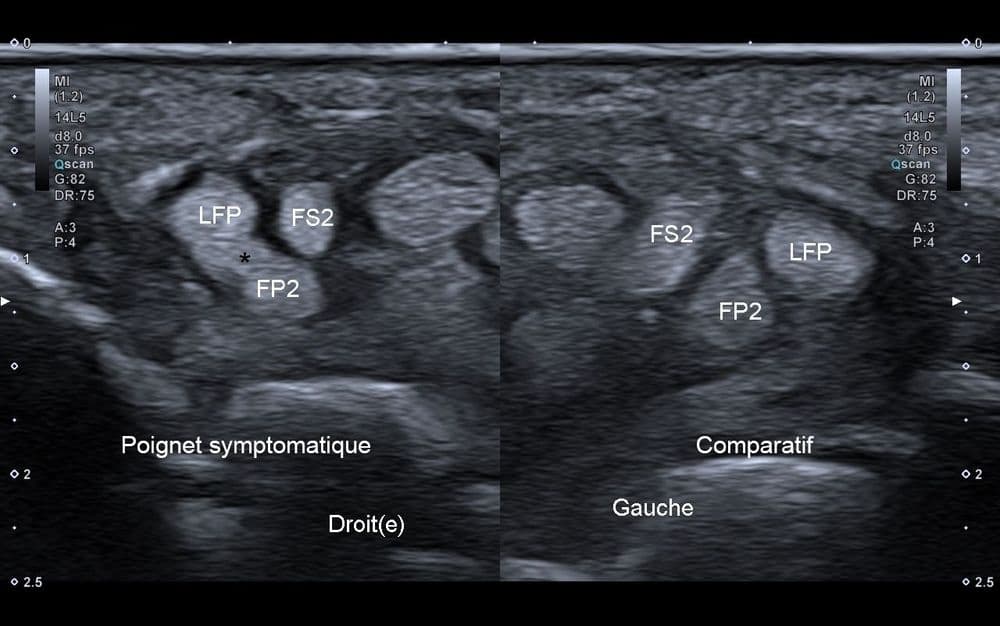

Le syndrome de Linburg-Comstock est une variante anatomique tendineuse entre le long fléchisseur du pouce et le fléchisseur profond de l'index.

US